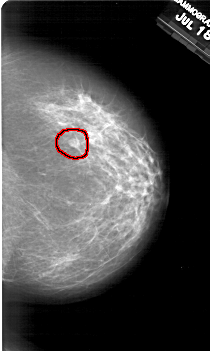

A_2001_1.LEFT_MLO

LEFT_MLO LINES 6196 PIXELS_PER_LINE 3886 BITS_PER_PIXEL 12 RESOLUTION 43.5 NON_OVERLAY

RIGHT_MLO LINES 6151 PIXELS_PER_LINE 3976 BITS_PER_PIXEL 12 RESOLUTION 43.5 OVERLAY

FILE: A_2001_1.RIGHT_MLO.OVERLAY

TOTAL_ABNORMALITIES 1

ABNORMALITY 1

LESION_TYPE MASS SHAPE OVAL MARGINS OBSCURED

ASSESSMENT 2

SUBTLETY 3

PATHOLOGY BENIGN

TOTAL_OUTLINES 1

BOUNDARY